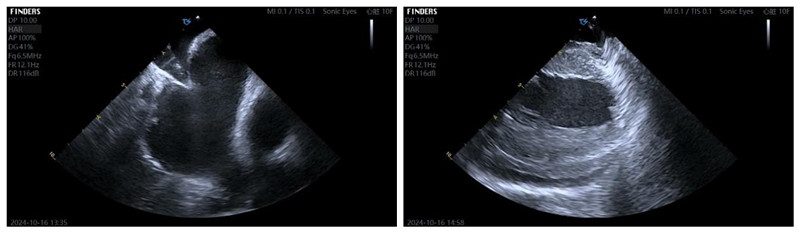

术中ICE指导穿刺并且时刻监测心包

消融图和术后心房基质图

经过治疗病人恢复正常窦性心律

手术过程中,医生首先通过血管插入超声导管,利用超声技术在心腔内构建心脏的三维模型。然后,医生会在三维模型的指引下,将消融导管精确地送到心脏的特定部位。通过释放脉冲能量,成功消除患者心房内触发房颤的异常电位,患者恢复正常的窦性心律。整个手术在局麻下进行,历时一小时左右。患者术后恢复良好,无任何不良反应。